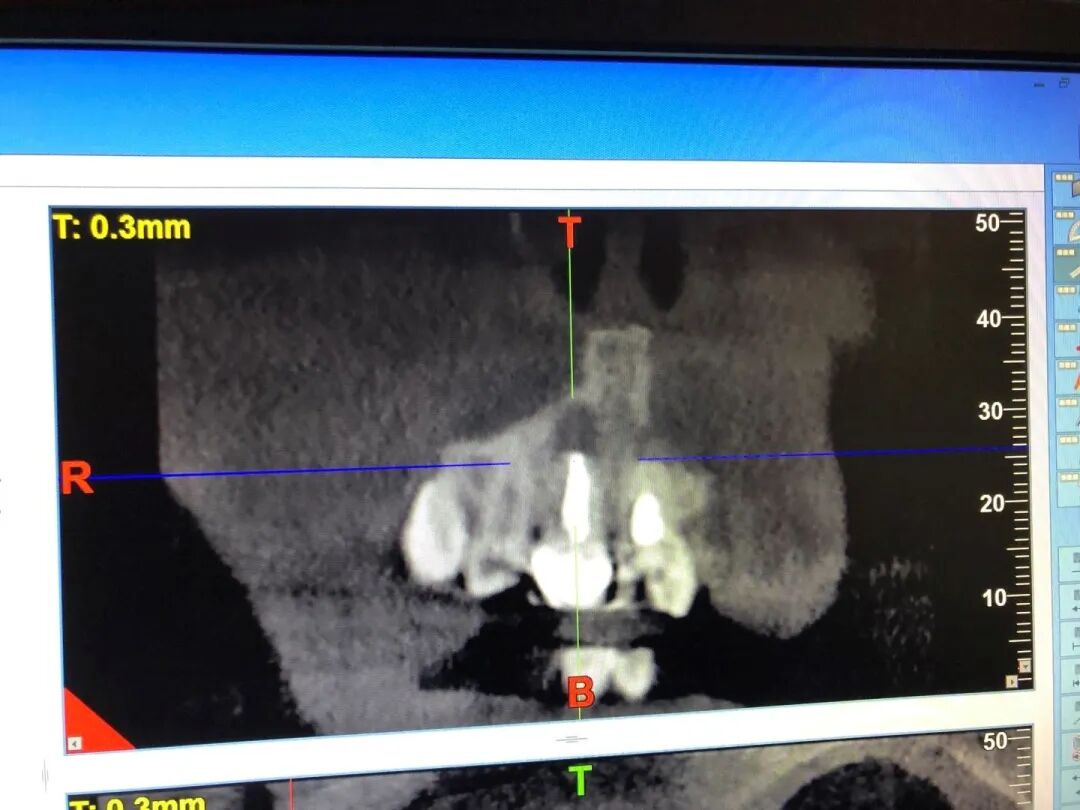

根尖囊肿CT正视图

看到两个黑色鼻孔了吗?再往上长就要长穿鼻孔啦!

| 作者供图